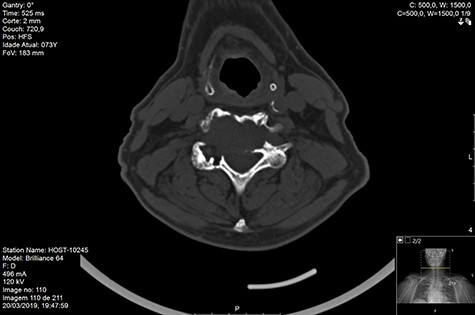

MRI and CT scans performed at 90 days post-radiation therapy showed an arrest of further progression of instability and resolution of the lytic lesion (Figs 7–13).